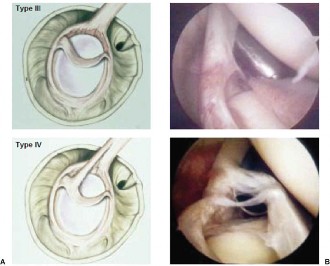

The correct answer is (B). The Snyder classification of SLAP tears is the first widely used classification systems for SLAP tears and consists of types I to IV (see Fig. 2–22A–B and Table 2–3). In type I tears (Answer A), there is fraying of the glenoid edge of the superior labrum, but the biceps tendon and superior labrum are both firmly attached to the biceps anchor and glenoid edge. In type II tears (Answer B), the biceps tendon and the superior labrum are detached from the superior glenoid edge and biceps anchor. In type III tears (Answer C), there is a bucket-handle tear of the superior labrum, but the remainder of the superior labrum and biceps tendon remain firmly attached to the glenoid rim and biceps anchor. In type IV tears (Answer D), there is a bucket-handle tear of the superior labrum that extends into the biceps tendon with extension of parts of the labral flap or biceps tendon into the joint space, and the remainder of the labrum and biceps tendon remain firmly attached to the glenoid rim and biceps anchor. Type V tears (Answer

E) do not exist. Complex lesions do exist and typically consist of a combination of type II and IV tears.

Figure 2–22(A–B) Snyder classification of rotator cuff tears in cartoon and arthroscopic views. (From Mileski RA, Snyder SJ. Superior labral lesions in the shoulder: pathoanatomy and surgical management. J Am Acad Orthop Surg. 1998;6(2):121–131.)